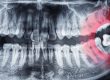

Ortopantomografia (OPT): panoramica iniziale per valutare il profilo osseo.

TC ATM: per analisi dettagliata delle strutture ossee.

Risonanza Magnetica (RMN): gold standard per visualizzare il disco articolare, eventuali infiammazioni e versamenti articolari.